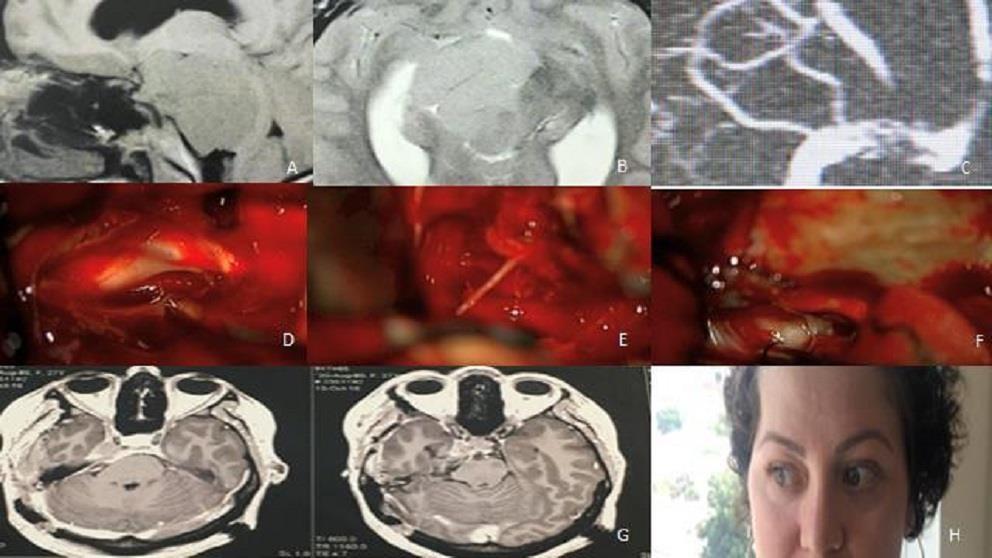

Figura 14: El abordaje petroso posterior está indicado para meningiomas petroclivales con inserción en el clivus medio y superior (A) y extensión en la fosa media (B). La venografía por resonancia magnética muestra el drenaje de la vena de Labbé en la unión de los senos transverso y sigmoideo (C). Imagen intraoperatoria del nervio oculomotor (D) y troclear (E) después de la resección del tumor. El facial está dentro del bloque óseo (*) y no necesita exponerse (F). Resonancia magnética con gadolinio postoperatorio (G y H). Paciente sin paresia postoperatoria de los nervios craneales (I).